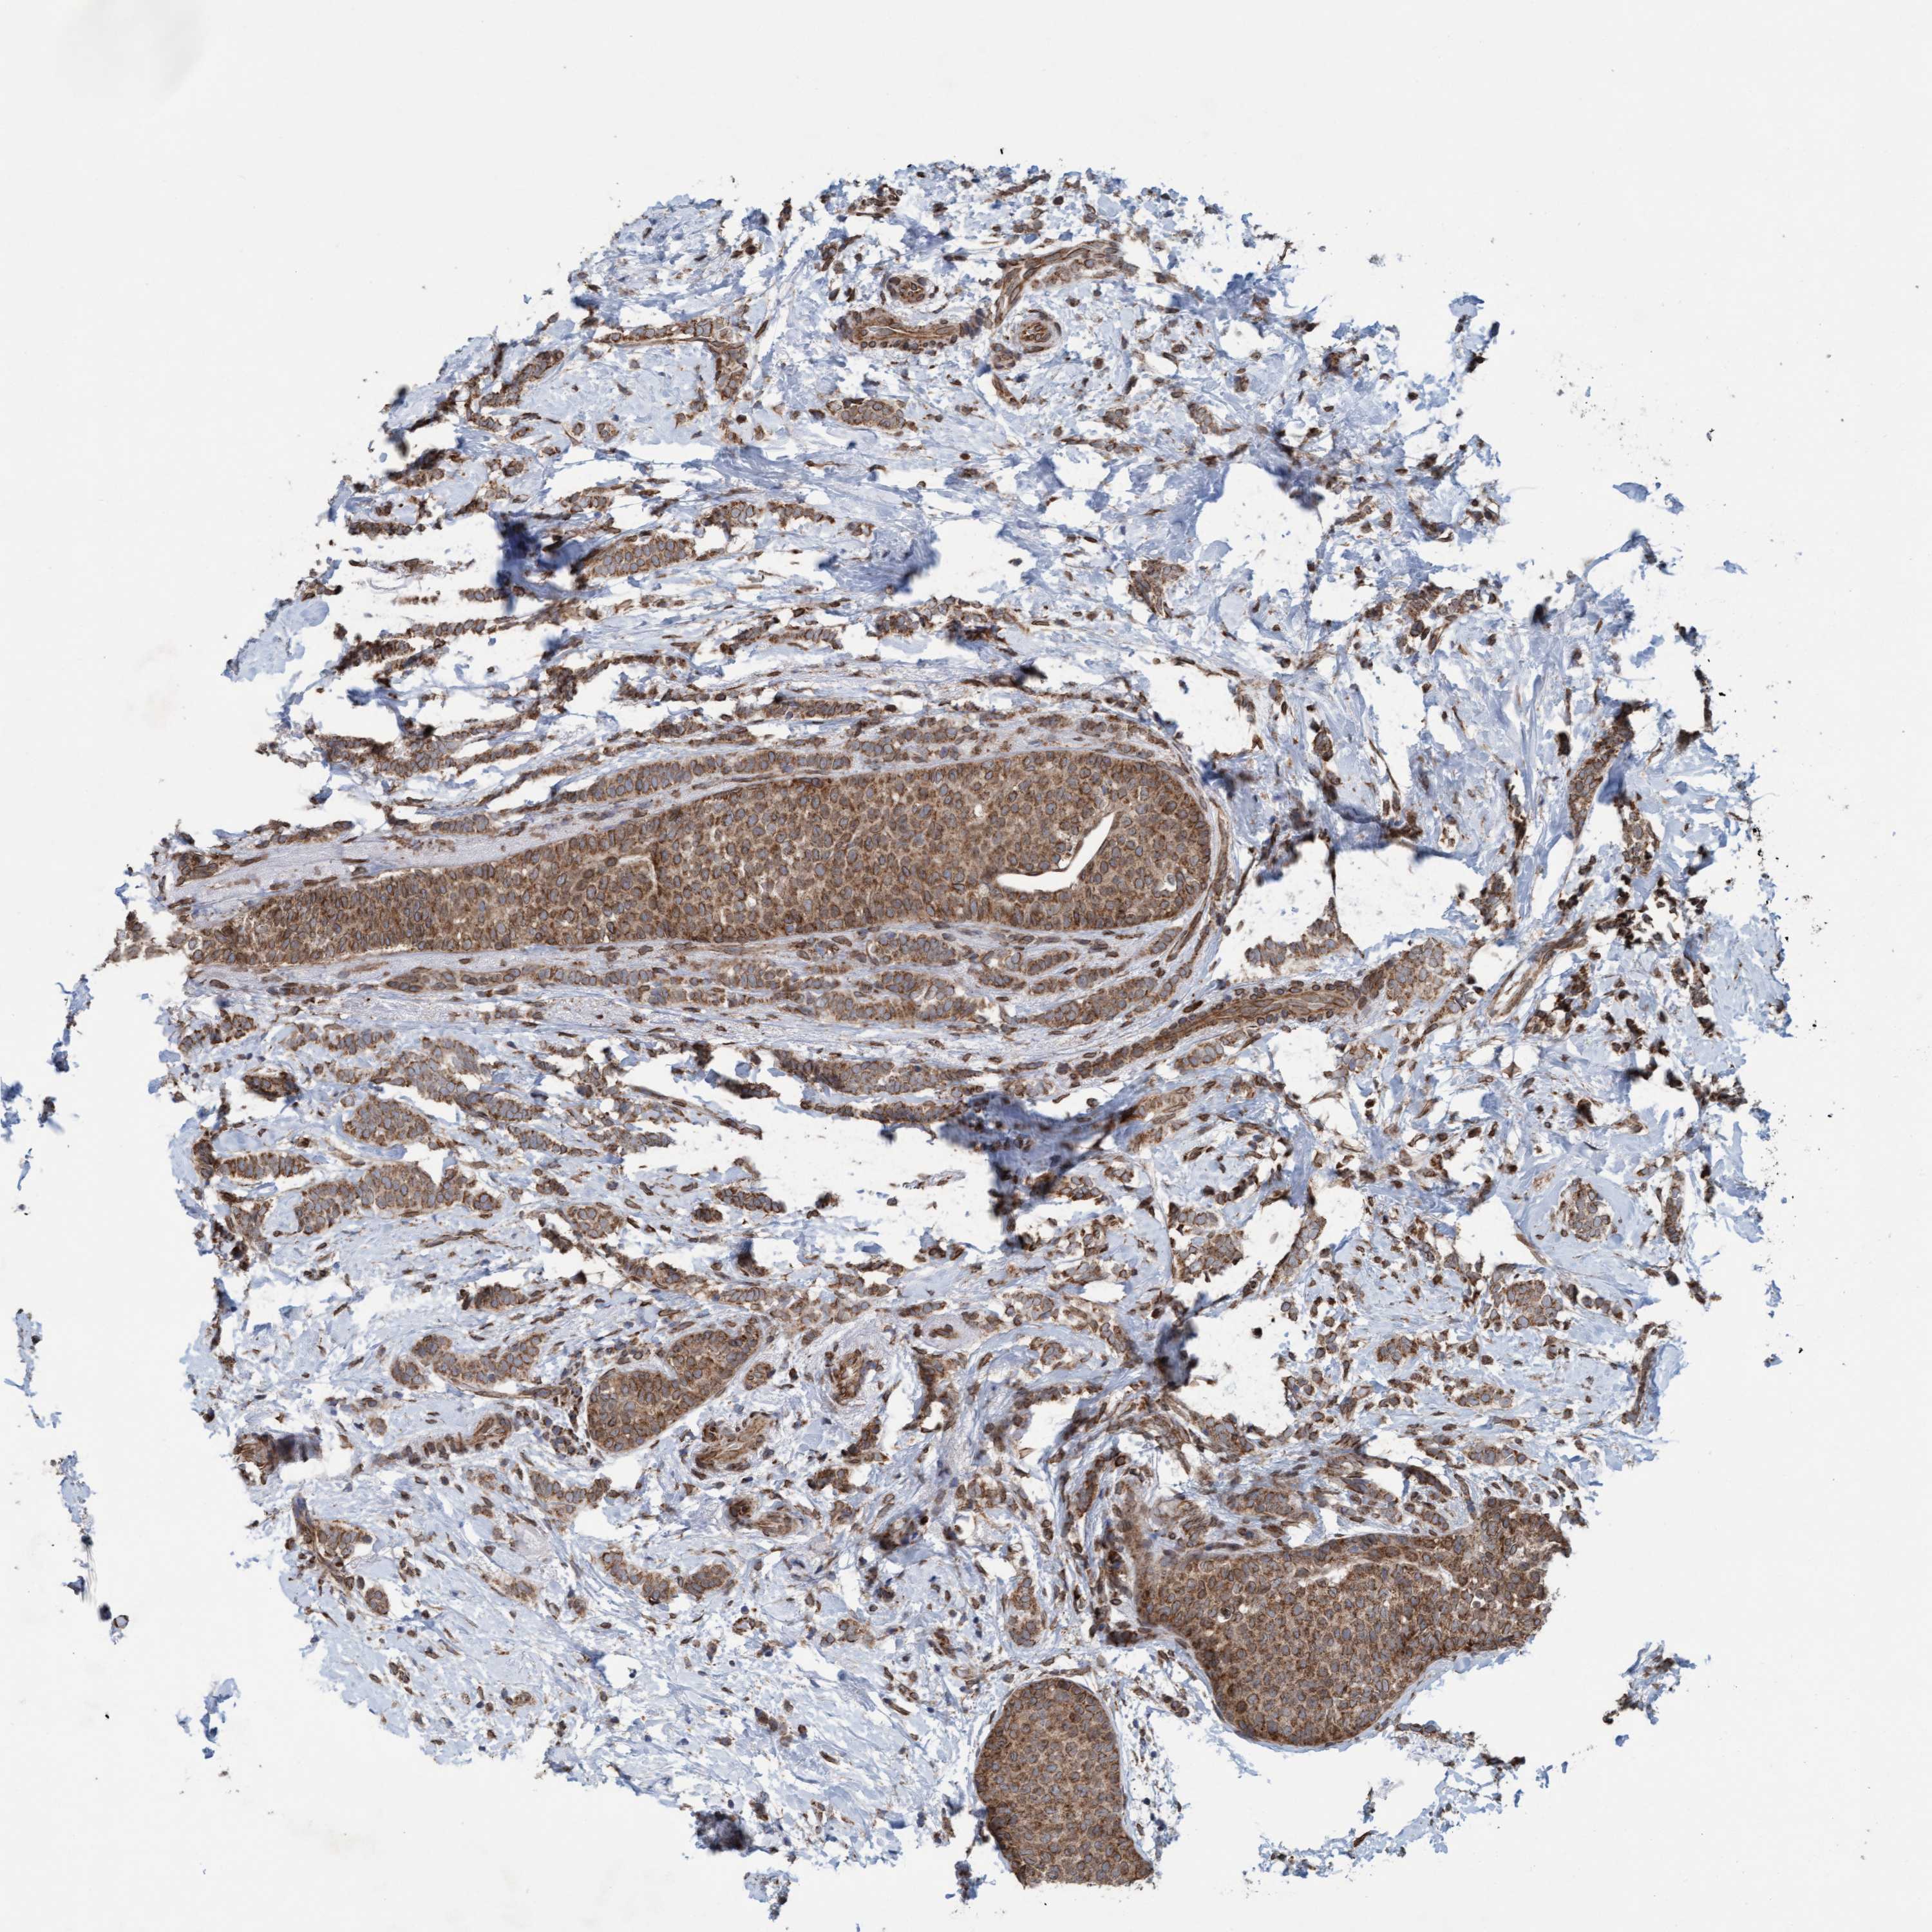

CANCER BREAST CANCER Show tissue menu

BRCA TCGA BRCA VALIDATION PROTEIN EXPRESSION